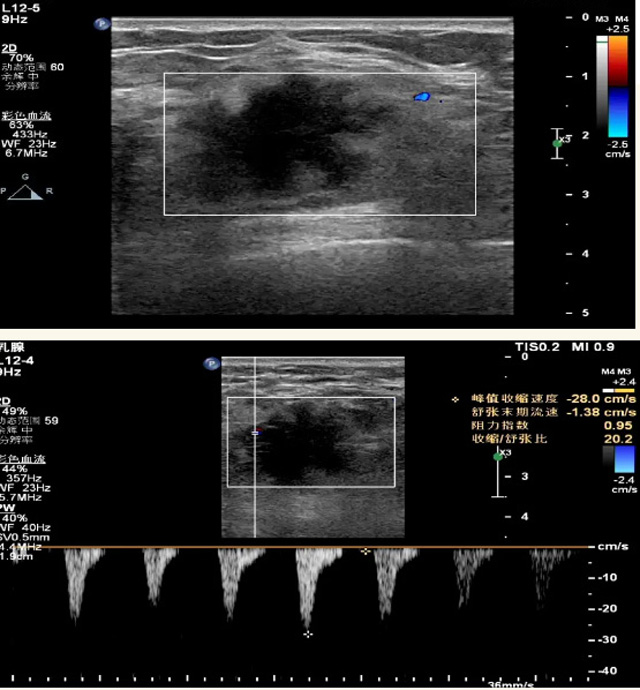

乳腺B超磁共振MRI對(duì)乳腺的檢查效果怎樣?

乳腺B超檢查無(wú)輻射,對(duì)囊性病變敏感,可以實(shí)時(shí)觀察病灶。超聲引導(dǎo)活檢跟手術(shù)前的定位。就是它對(duì)于微小的鈣化查出率比鉬靶稍微差點(diǎn)。磁共振MRI檢查也是是沒(méi)有輻射的,對(duì)備孕跟已經(jīng)懷孕的人士比較友好。不用擔(dān)心這個(gè)輻射影響胎兒?jiǎn)栴}。對(duì)乳腺病灶敏感性較高,致密乳腺病灶、乳腺癌的復(fù)發(fā),準(zhǔn)確鑒別囊性及實(shí)性病變。可以幫助臨床醫(yī)生判斷惡性、良性病變。但是MRI磁共振對(duì)微小鈣化不明顯,微鈣化還是鉬靶靠譜點(diǎn)。檢查時(shí)間比較長(zhǎng),有偽影的影響。費(fèi)用相對(duì)B超,鉬靶高很多。

乳腺B超

磁共振MRI

乳腺檢查需要避開(kāi)經(jīng)期,經(jīng)期后一周比較合適。設(shè)備檢查時(shí)候壓10秒鐘左右,不會(huì)有很大的疼痛,稍微有點(diǎn)不適應(yīng)。鉬靶輻射劑量小,腺體越厚,所受劑量也會(huì)有所增高。次診斷性的X線檢查劑量,也達(dá)不到能造成胎兒或者胚胎損傷的劑量。乳腺B超跟磁共振MRI就沒(méi)有輻射。胸小或者假體植入也可以做檢查,乳腺組織曝光野內(nèi),圖像受干擾的情況降到最低,從而保證結(jié)果的準(zhǔn)確性。